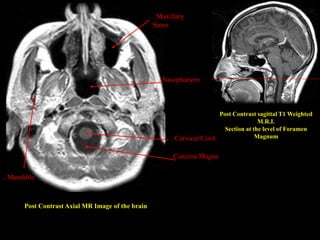

Post Contrast Axial MR Image of the brain

Post Contrast sagittal T1 Weighted

M.R.I.

Section at the level of Foramen

Magnum

Cisterna Magna

. Cervical Cord

. Nasopharynx

. Mandible

. Maxillary

Sinus